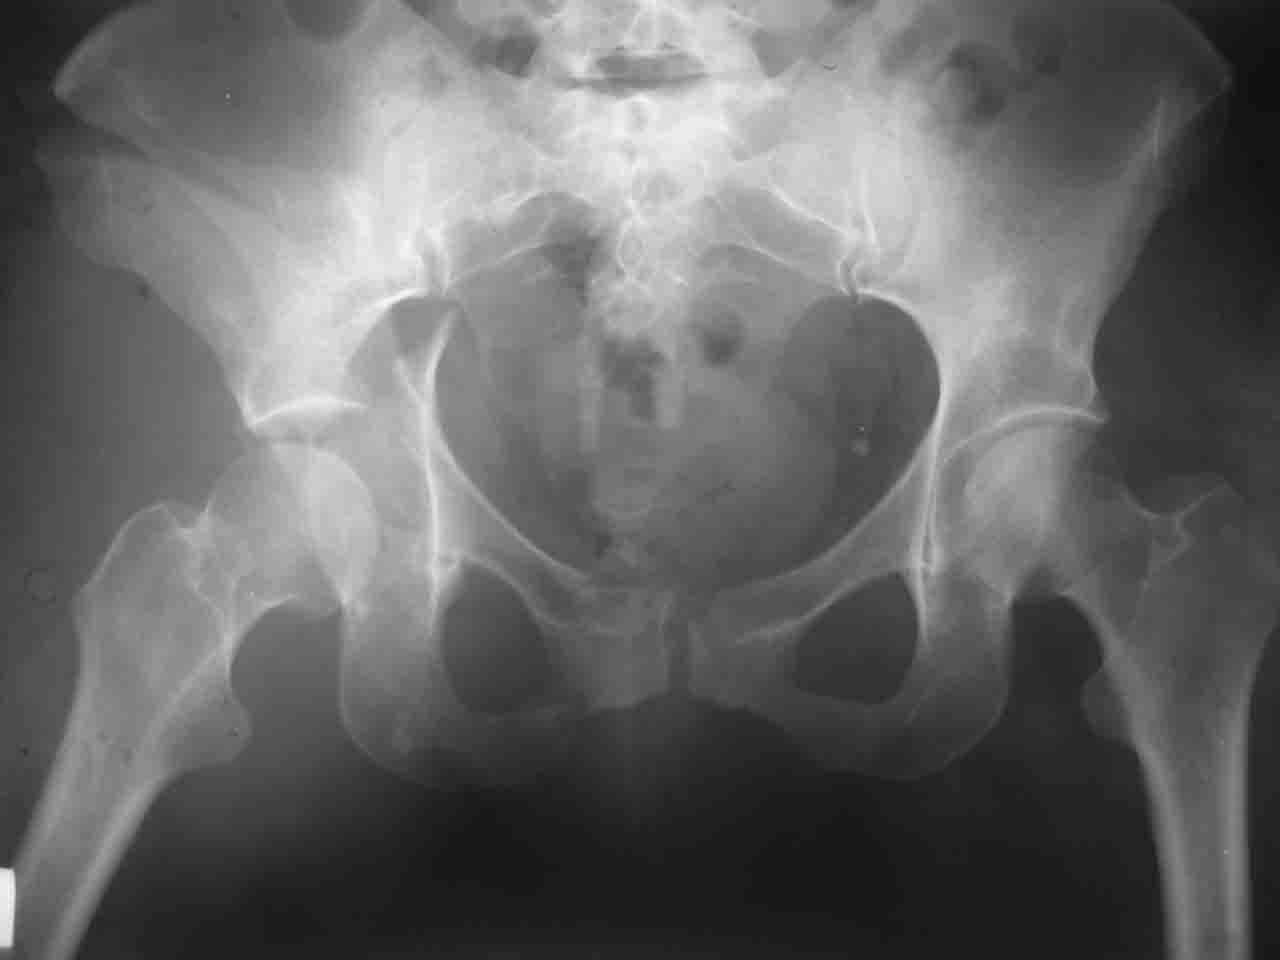

А какой отдел вертлужной впадины более важен передний или задний? Чем был обусловлен выбор доступа к суставу? Проще говоря, почему вы пошли передним доступом на двухколонный перелом? Мне понятны ваши сомнения, когда не удется сделать все что хотелось бы. В данном случае доступ должен быть чрезвертельным боковым (как и советовал Рунков) или двумя доступами.

> А какой отдел вертлужной впадины более важен - передний или задний?

Однозначного ответа у меня нет : лучше быть богатым и здоровым , чем бедным и больным :-))

Логика подсказывает, что все-таки лучше иметь анатомически полноценную впадину, хотя ранее упоминалось состояние вторичной конгруэнтности и одно наблюдение у меня есть, когда у больного с полностью нарушенной анатомией впадины и подвывихом головки бедра кзади и кверху боли отсутствовали при относительно достаточном для стиля жизни больного объёме движений. Но это только одно наблюдение и кроме перелома впадины у этогобольного была и тяжелая ЧМТ в анамнезе. Основываясь на формулировке структуры ацетабулюм Э. Летурнеля - как перевернутой буквы Y, впадина для полноценной функции сустава должна иметь сферичность, соответствующую размеру головки бедра и если один из компонентов в дефиците, то функциональные последствия рано или поздно проявятся.

> передним доступом на двухколонный перелом?

Илеофеморальный доступ не совсем передний и сравнительно с илеоингвинальным, и Кохера-Лангенбека открывает весь наружный таз кроме самых передних отделов лонных костей, фиксацию которых я не ставил в задачу. Обширность диссекции, большая длительность операции и более высокий риск гетерооссификации - отрицательные моменты в обмен на возможность легче ориентироваться.

Вопрос доступа к вертлужной впадине при остеосинтезе задача не простая. Конечно, у Летурнеля и Тайла всё давно описано, нам остается только брать на вооружение. Но сами понимаете, что не бывает двух одинаковых ситуаций, поэтому в каждом случае вопрос решается сугубо индивидуально. Наша главная цель - восстановить анатомию с нанесением минимальной дополнительной травмы тазобедреннному суставу, думаю с этим никто не поспорит. Расширенный илиофеморальный доступ уж слишком травматичен (как сказал один коллега "таз лежит отдельно, больной отдельно").Стоит ли делать из пациента анатомический препарат для того чтобы легче ориентироваться. Да и нужно ли собирать всю "мозаику"? Мы применяли при таких операциях своеобразную операционную хитрость - сначала устраняли грубое смещение крыла под гребнем с фиксацией так называемой "плавающей" пластиной (временно фиксированной на двух винтах)- доступ или продлевали боковой, или делали небольшой дополнительный разрез над гребнем. Это позволяло устранить грубое смещение и захождение отломков тела повздошной кости, что значительно облегчало репозицию и остеосинтез впадины над сводом. Основное внимание конечно же уделяли нагружаемому задне-верхнему отделу. Сообщите ваш адрес, пришлю схемы и рентгенограммы.